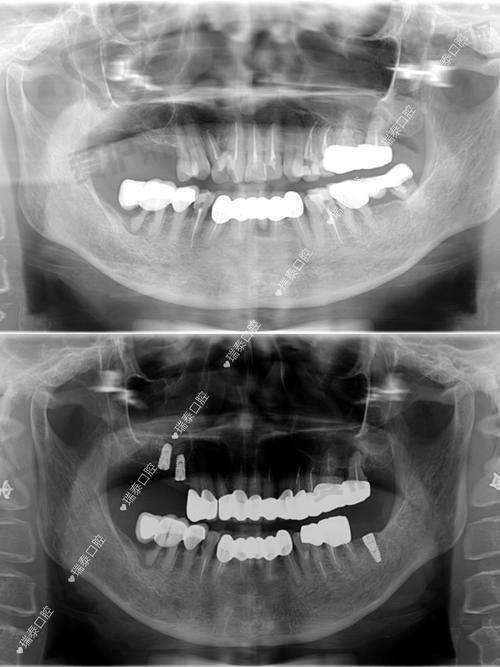

重庆团圆口腔医院的服务保护

重庆团圆口腔医院为患者提供了全方面的服务保护。在术前,医院会为患者进行全方面的口腔检查,包括口腔X光片、CT扫描等,以正确了解患者的口腔状况。李志锋医生会根据检查结果,为患者制定个性化的种植方案,并向患者详细解释手术过程和注意事项。

为了让大家更好地了解重庆团圆口腔医院李志锋医生开展的以色列种植牙项目,下面为大家分享一个患者实例。张先生是一位50多岁的患者,由于长期的牙齿缺失,导致咀嚼功能下降,面部也出现了一定程度的凹陷。他在朋友的推荐下来到了重庆团圆口腔医院。

李志锋医生为张先生进行了详细的检查后,建议他进行以色列种植牙手术。在与张先生充分沟通后,制定了适合他的种植方案。手术过程非常顺利,张先生在术后修复得也特别快。现在,张先生已经成功戴上了种植牙,他的咀嚼功能得到了明显改善,面部也修复了饱满。张先生对种植成效非常满意,他说:“没想到种植牙能让我的生活发生这么大的改变,感谢重庆团圆口腔医院和李志锋医生。”